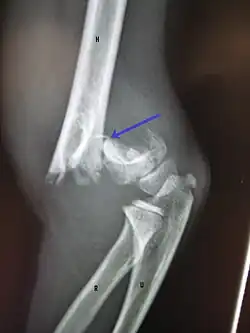

On lateral view of the elbow, there are five radiological features should be looked for: tear drop sign, anterior humeral line, coronoid line, fish-tail sign, and fat pad sign/sail sign (anterior and posterior).[3][8]

Fat pad sign/sail sign - A non-displaced fracture can be difficult to identify and a fracture line may not be visible on the X-rays. However, the presence of a joint effusion is helpful in identifying a non-displaced fracture. Bleeding from the fracture expands the joint capsule and is visualized on the lateral view as a darker area anteriorly and posteriorly, and is known as the sail sign.[8]

Anterior and posterior sail sign in a child who has a subtle supracondylar fracture -